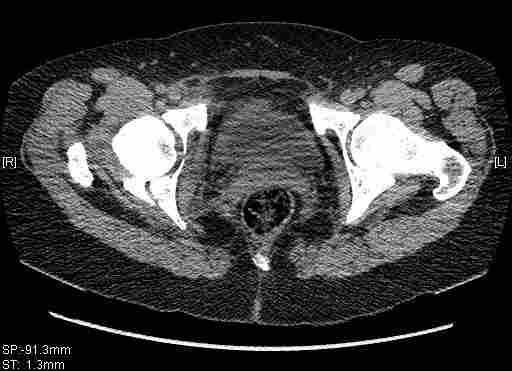

[Ortho] [2/2] Re: Т-образный перелом вертлужной впадины

Остальные срезы.